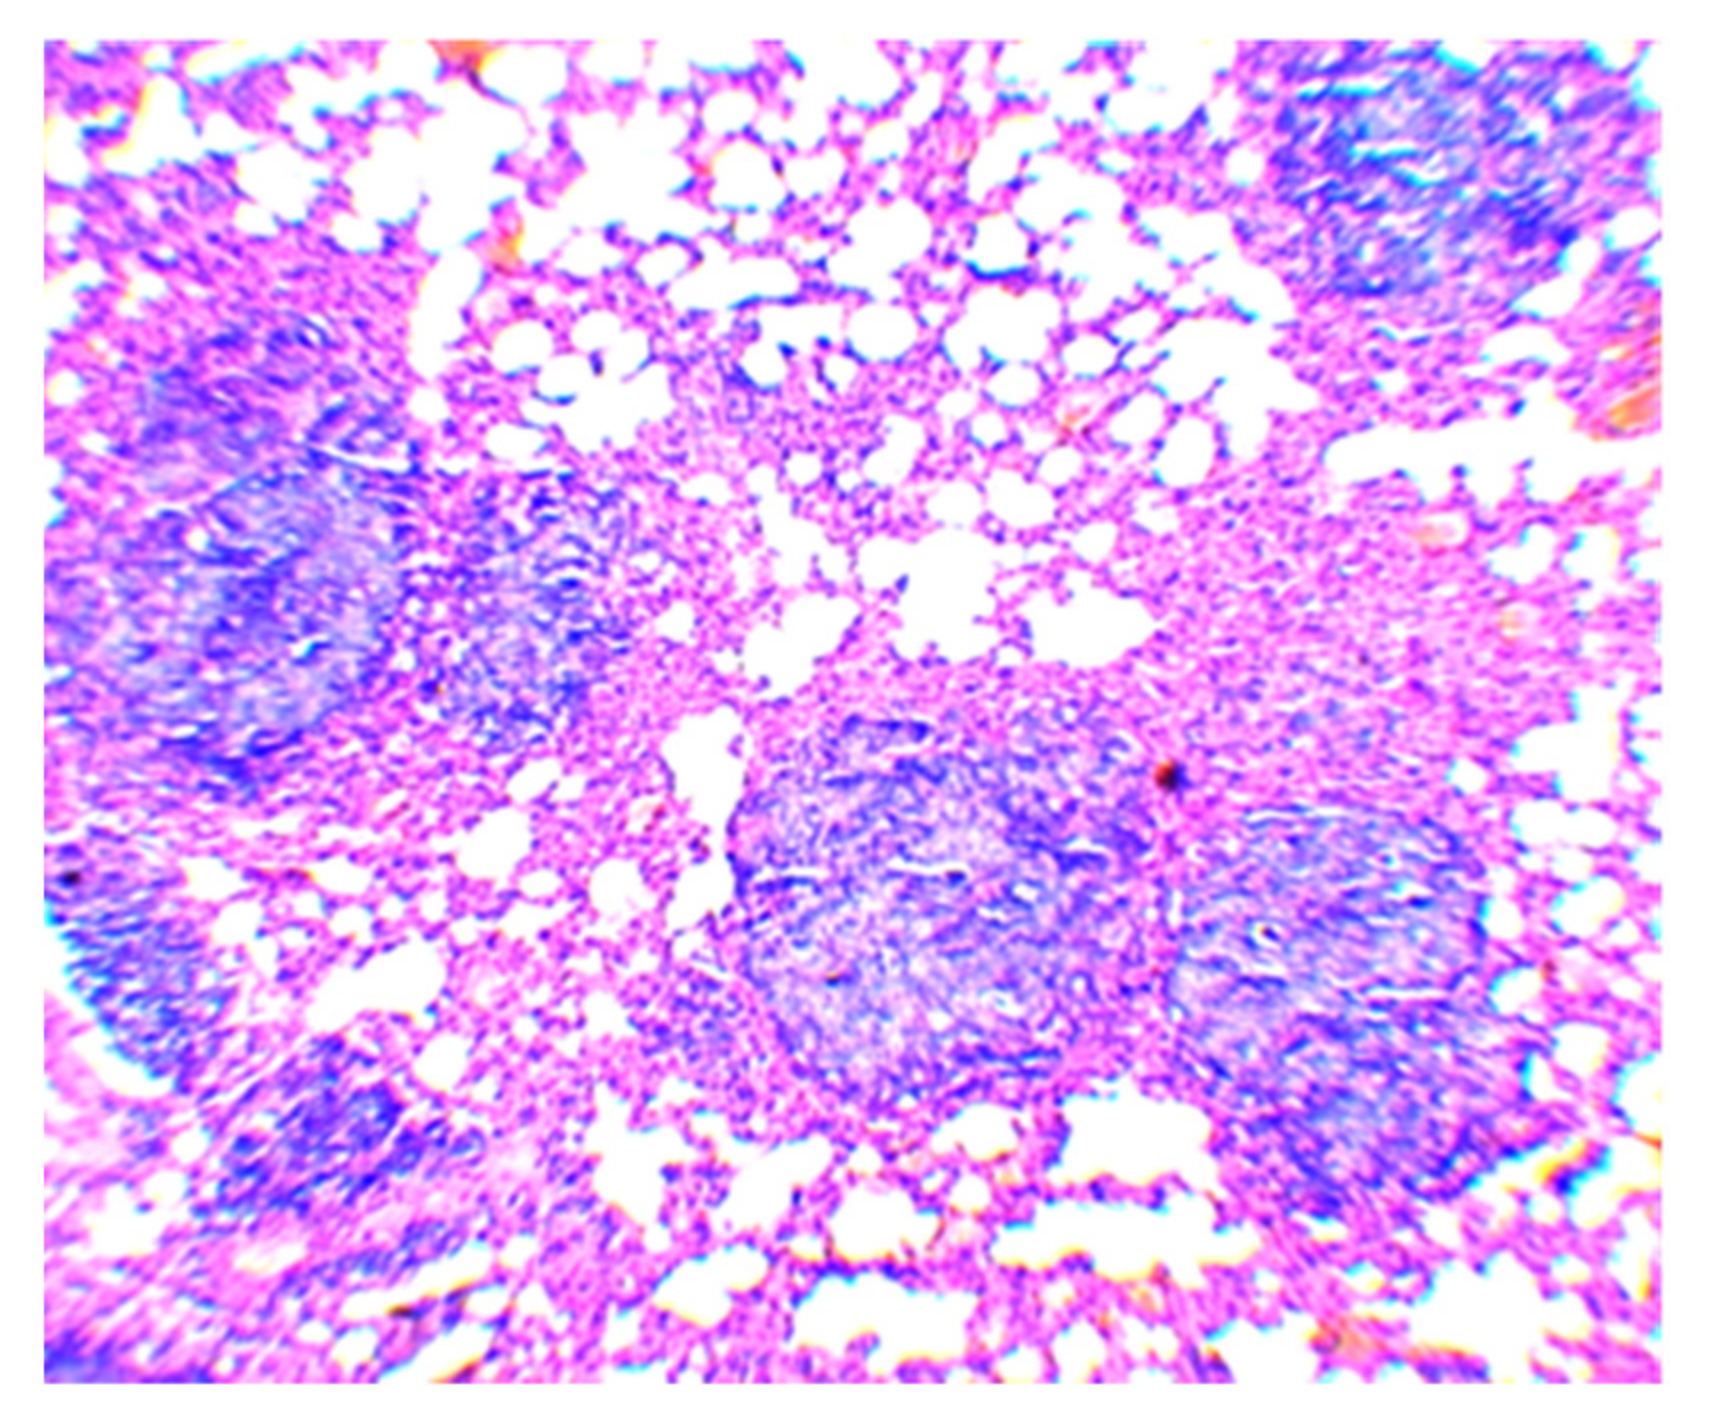

| Group No. | BCG Vaccine | Compound | Mean Follicle Area (µm2) | Mean Follicle Diameter (µm) | Follicle Size Distribution by Diameter (µm) | Number of Follicles of the Same Size (%) |

|---|---|---|---|---|---|---|

| 1 | − | − | 34,103.0 ± 2766.5 | 203.0 ± 8.8 | 70–100 | 3.3 |

| 110–160 | 23.3 | |||||

| 170–220 | 40.0 | |||||

| 230–270 | 26.7 | |||||

| 280–300 | 6.7 | |||||

| 2 | + | Betulinic acid | 37,478.8 ± 4532.1 | 216.3 ± 14.0 | 70–100 | 6.7 |

| 110–160 | 16.7 | |||||

| 170–220 | 33.3 | |||||

| 230–270 | 25.7 | |||||

| 280–300 | 16.7 | |||||

| 3 | + | Betulin | 19,080.7 ± 1905.0 1 | 147.0 ± 9.0 2 | 70–100 | 10.0 |

| 110–160 | 53.5 | |||||

| 170–220 | 36.7 | |||||

| 4 | + | Betulonic acid | 11,458.4 ± 1240.7 2 | 115.7 ± 6.5 2 | 70–100 | 43.3 |

| 110–160 | 46.7 | |||||

| 170–190 | 10.0 | |||||

| 5 | + | − | 20,742.3 ± 2386.4 1 | 155.0 ± 9.1 2 | 70–100 | 13.3 |

| 110–160 | 50.0 | |||||

| 170–220 | 23.4 | |||||

| 230–250 | 13.3 |